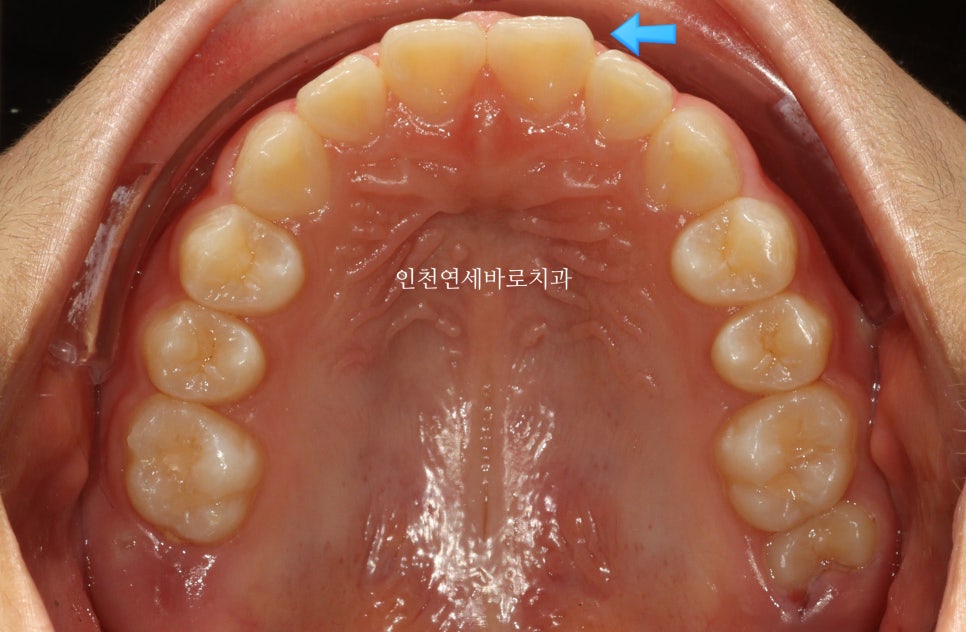

앞니가 튀어나와있고, 삐뚤삐뚤, 그리고

#과개교합

도 있는 아이었습니다.

거의완성되었습니다.

거의 라고 말하는 이유는 저희 의료진 눈에는 아주아주 미세한 부분이 마음에 들진 않아서요.

화살표 부분이 약간 아쉬웠기 때문입니다.

| 초기 상태 | 앞니 돌출, 배열 불량, 과개교합 |